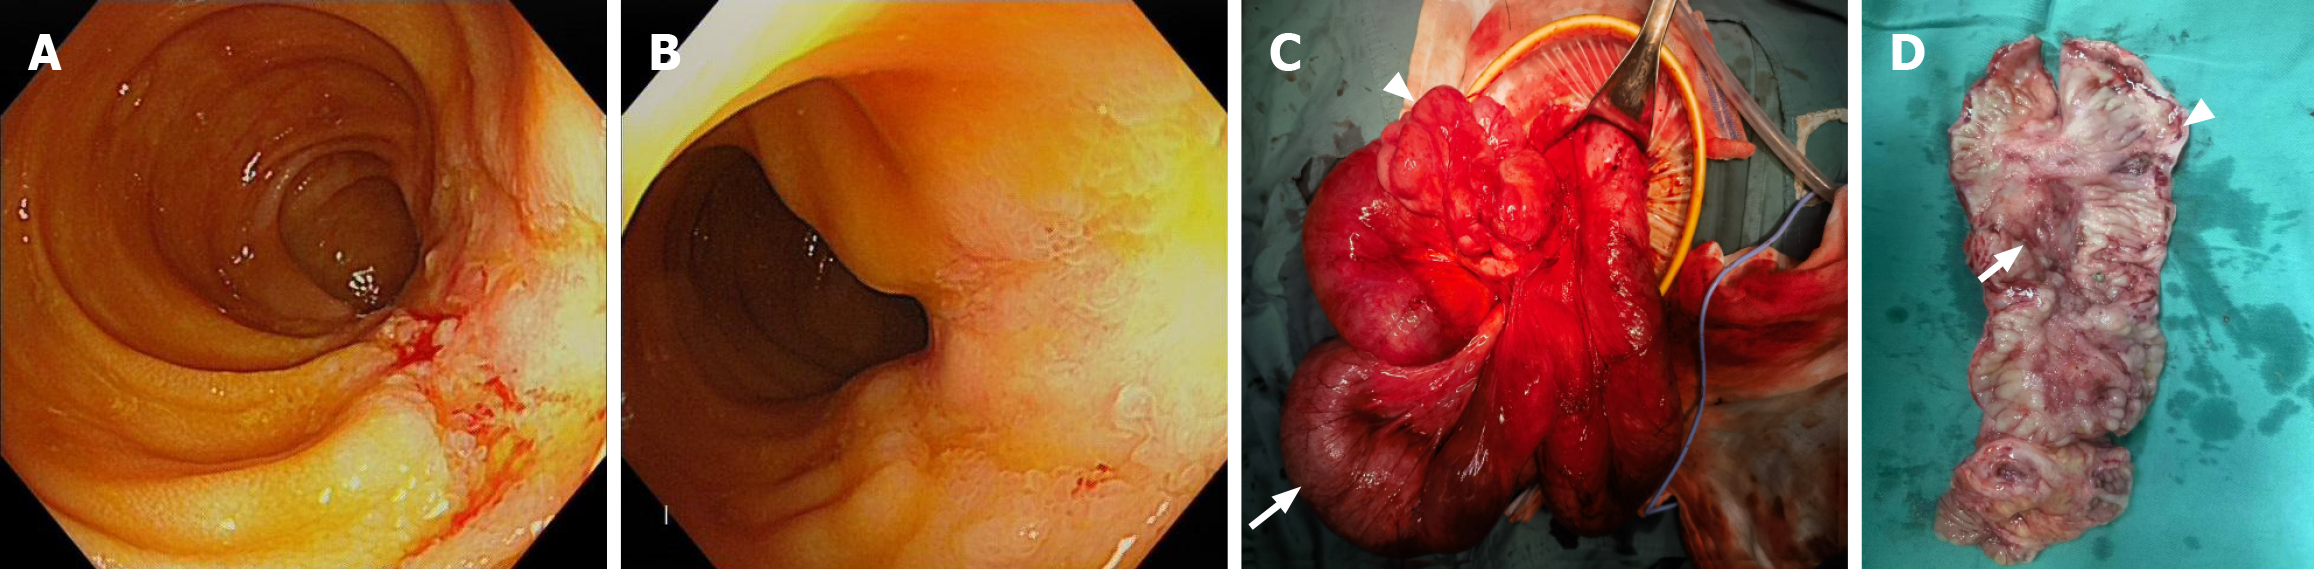

Figure 3 Endoscopic and specimen images.

A and B: Terminal ileum, approximately 8 cm long longitudinal ulcer, bleeding on the mucosal surface, surrounding small granular hyperplasia; C: Surgical image, tortuous and lumpy terminal ileum (triangle), dilated and edematous proximal small bowel (arrow); D: Resected bowel, intestinal wall thickening with a constricted ring (triangle) and a longitudinal ulcer (arrow) in the adjacent area.